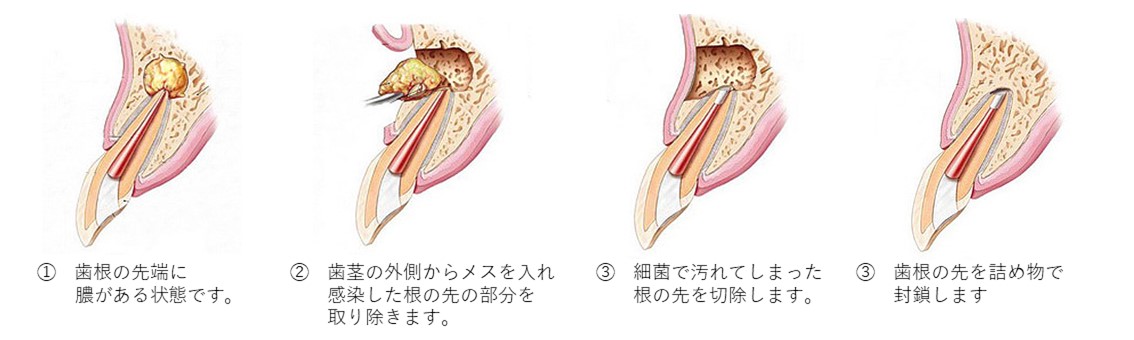

歯根端切除術(しこんたんせつじょじゅつ)

根の治療をしても膿が消えない場合、外科的に歯ぐきからアプローチし、感染している「根の先端部分」を直接切り取り、膿の袋を除去する方法です。

マイクロスコープを用いることで、非常に高い精度で行えます。